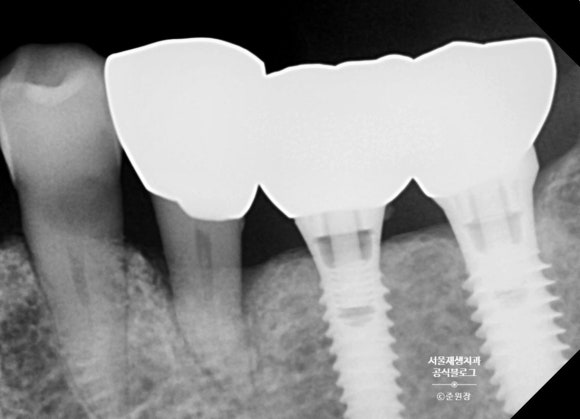

치근단 사진을 통해 정확한 치아 상태를 살펴봐요.

치근단 사진을 찍어보았습니다.

파노라마 사진 = 단체사진

치근단 사진 = 증명사진

이라고 환자분들께 설명드리곤 합니다.

단체 사진을 아무리 확대해도 얼굴에 있는 점이나 주근깨, 미세한 주름까지는 보이지 않지요?

정확한 진단이 필요한, 혹은 치료를 앞둔 치아는 치근단 엑스레이를 촬영하여 현상태를 보다 면밀히 파악하는 것이 필수입니다.

(모두 건강보험진료이기 때문에 비용은 몇 천원에 불과합니다.)